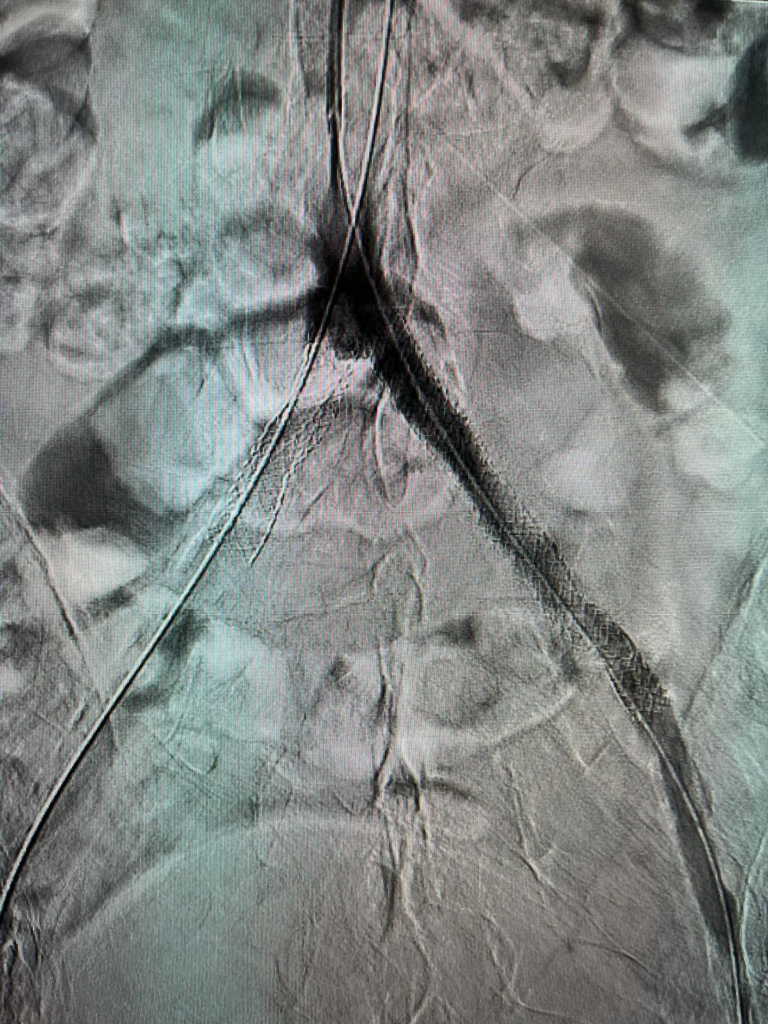

În cadrul procedurii au fost dilatate arterele afectate încă de la terminația aortei și rădăcina membrului inferior drept și au fost implantate 3 stenturi după pregătirea leziunilor țintă prin dilatare cu baloane de angioplastie. Două dintre stenturi au fost puse alăturate unul la celălalt la nivelul bifurcației aortei înspre membrele inferioare și s-a refăcut astfel această bifurcație care era afectată ateromatos sever și provoca simptomatologie invalidantă a pacientului. Al treilea stent a fost montat la nivelul arterei iliace care deservește membrul inferior stâng unde exista o îngustare semnificativă. Rezultatul final este unul bun cu circulația corectă a sângelui înspre membre.

Ajutorul oferit acestui pacient a fost posibil prin colaborarea excelentă în cadrul unei echipe mixte de cardiologie și radiologie, în cadrul programului național de Radiologie Intervențională coordonat de dr. Florin Grosu.